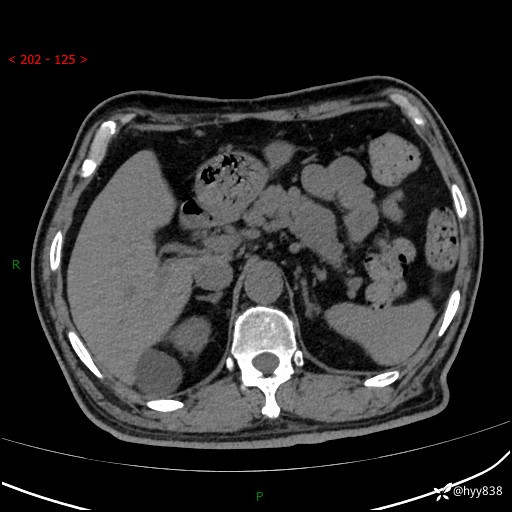

【检查】:胰腺CT平扫+增强